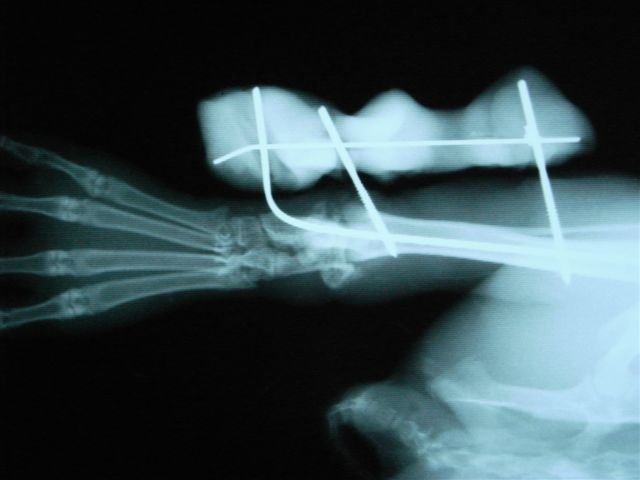

右頚骨の骨端線で骨折。

エポキシパテと髄内ピンで整復して固定

骨折する場所は太股の骨(大腿骨)、すねの骨(頸骨)、背骨(脊椎)です。後ろ足の力が強いために起こります。足の骨の場合、骨の中に金属の棒(ピンニング)やプレートで固定をして外側から固定をして、動かないようにケージに入れておきます(ケージレスト)。1ヶ月から2ヶ月ぐらいかかると思ってください。

関節に近い骨折だと固定が関節ごと固定するので稼動域が狭くなりやすい。